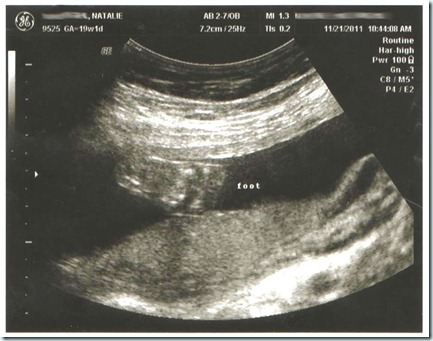

21 weeks and counting…

Here’s where we are this week:

Your baby now weighs about three-quarters of a pound and is approximately 10 1/2 inches long — the length of a carrot. You may soon feel like she's practicing martial arts as her initial fluttering movements turn into full-fledged kicks and nudges. You may also discover a pattern to her activity as you get to know her better. In other developments, your baby's eyebrows and lids are present now, and if you're having a girl, her vagina has begun to form as well.

How far along: 21 weeks

This is because my bump has somehow mysteriously disappeared. Never mind, it’s not a mystery. The reason it has disappeared is because my son is trying to fall out. He just refuses to move up.

Do you see what I’m talking about? I am 20 weeks here.

Believe it or not, he was even lower than that throughout most of my ultra-sound.

Movement: Most days he moves quite a bit. It’s pretty sporadic, though. Lots of kicks here and there and the nothing for a while. I have to shake my belly from time to time or talk loudly to wake him up. If I could just attach an ultra-sound machine to myself 24/7, I wouldn’t have to do such things!

Next appointment: January 3rd. I had an appointment today (after I totally spaced and missed my appointment yesterday by accident), and everything checked out great. H/B was 149 average. He’s measuring on track. The u/s results were good. I won’t have to have the gestaional diabetes test until my 28th week, so I’m glad I don’t have to drink that nasty stuff anytime soon.